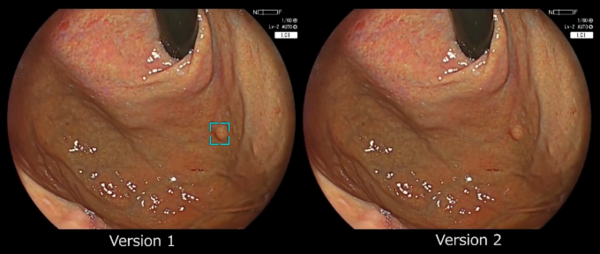

富士フイルムは,2020年に大腸内視鏡検査におけるポリープなどの病変検出および鑑別を支援するソフトウェア「EW10-EC02」*4を発売した。その後,2022年には,AI技術を活用して開発された上部消化管領域の内視鏡診断を支援する医療機器として日本で初めて薬事承認を受けた*5「EW10-EG01」を発売。「EW10-EG01」は,上部消化管の内視鏡検査時に胃腫瘍性病変や食道扁平上皮癌が疑われる領域をリアルタイムに検出するソフトウェアで,病変が疑われる領域を検出すると,対象領域を枠(検出ボックス)で囲って表示するとともに報知音を発して,医師による検出を支援する。

今回提供を開始する「EW10-EG01 Ver2.0」では,食道,胃ともに,高い感度の維持と特異度の向上を目指し,Ver1.0から内視鏡検査画像の学習量を全体で約1.6倍に増加させた。これにより,Ver1.0で認められた誤検出の低減が期待され,胃がん・食道がんの早期発見を支援する。

(上:Ver1.0*7 下:Ver2.0*8)

Ver1.0では誤検出し,Ver2.0では誤検出しなかった症例

Ver1.0,Ver2.0ともに検出した症例